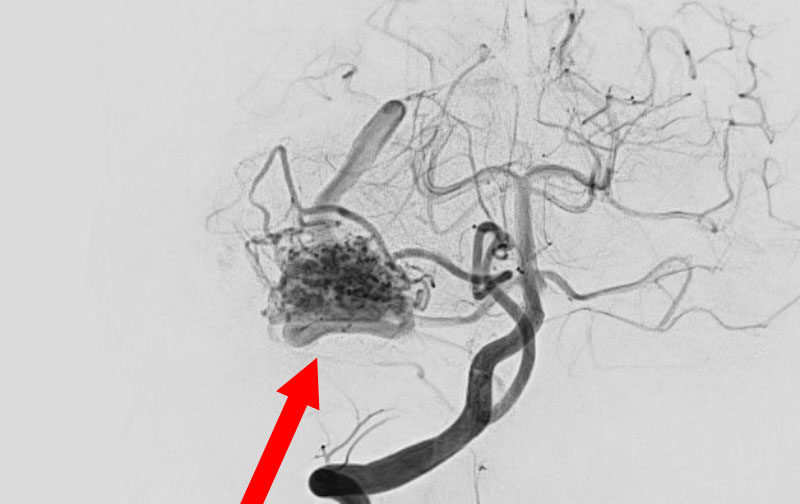

'26年3月

出血性脳動静脈奇形

10代

院内外来

No.1620 手術前

No.1620 手術中

No.1620 手術後